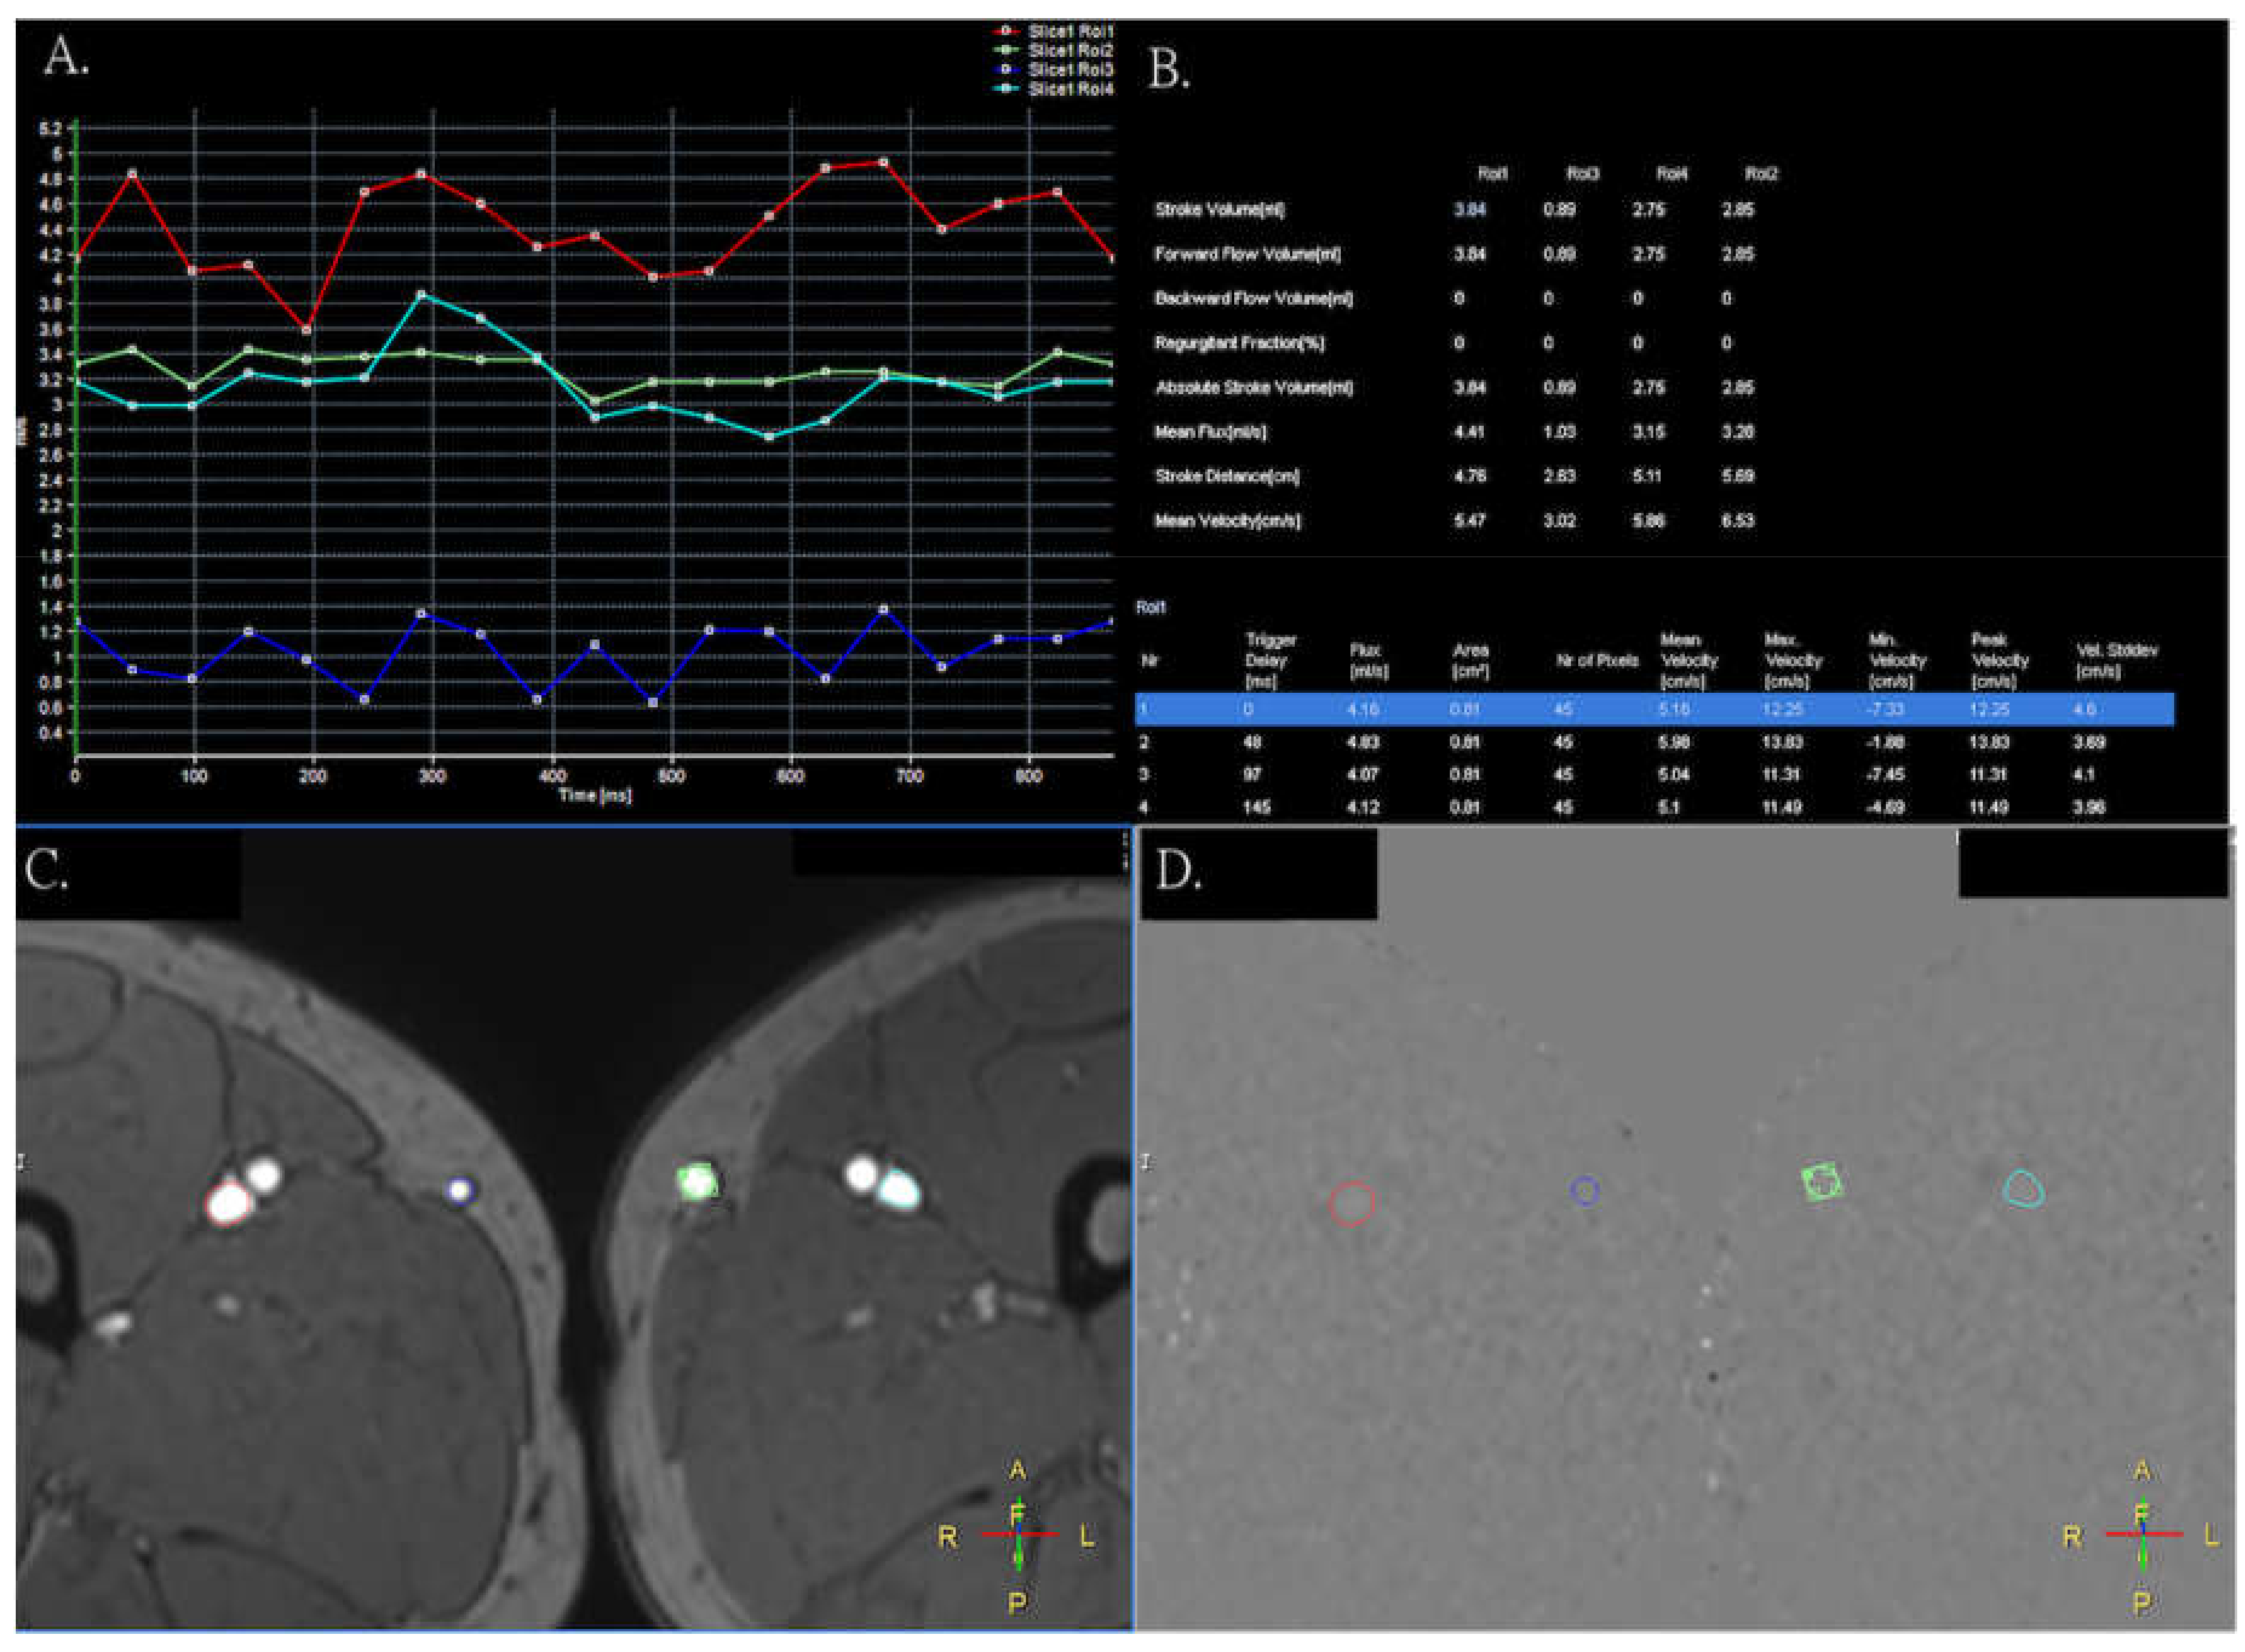

3. Results